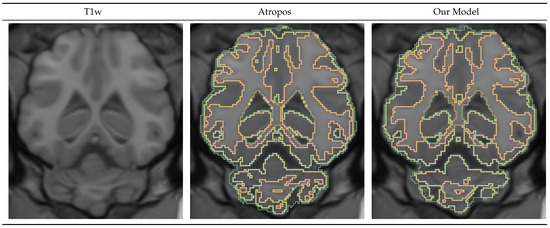

Figure 5 shows an axial slice of an example T1-weighted image, Atropos prediction, and our model prediction. Atropos is a tool aimed at human data, and the results produced for the minipig data were suboptimal, making the comparison harder. We can see that the produced masks were very similar. We observe that Atropos tends to oversegment the white matter, especially in the cerebellum region.

Figure 5.

Gray and white matter and cerebrospinal fluid segmentation mask visualization. Our model produced masks similar to the Atropos tool.

Table 6 shows the DICE and bAVD results for the GWC model performance on the test dataset compared with the Atropos results. We can see that the CSF performance was consistently the lowest and that the white matter had the highest DICE value. We observed a low distance error of bAVD 0.05 voxels for all masks, with a standard deviation of 0.01 voxels. Additionally, the results were hurt by the posterior cutoff point in the same way as in the ICV model, as both Atropos and our GWC model used the ICV mask as input.